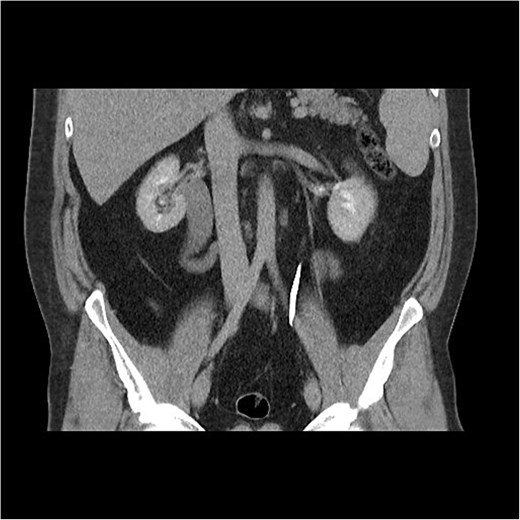

Initial work-up revealed microscopic haematuria and a mildly elevated creatinine of 156 μmol/L (65.4–119.3 μmol/L). A computerized tomogram (CT) urogram showed proximal hydroureteronephrosis with preserved renal cortex (Fig. 1). A diethylenetriamine pentaacetate (DTPA) renogram with diuretic showed accumulation of contrast then prompt excretion with administration of diuretic, suggesting partial obstruction or hypotonic collecting system (Fig. 2). At this point alternative diagnoses were considered, including RU. Ongoing severe right flank pain was noted despite multimodal analgesia and a right-sided nephrostomy was placed with immediate relief of pain and obstruction. Figure 3 shows the nephrostogram with S-shaped hydroureter. No further analgesia was required, and creatinine normalized (90 μmol/L). The case was discussed at a multidisciplinary meeting, wherein a unanimous diagnosis of RU was confirmed, and a plan for minimally invasive laparoscopic dissection and re-anastomosis of the ureter was made.

CT abdomen shows an S-shaped ureter with the right ureter passing behind the IVC.